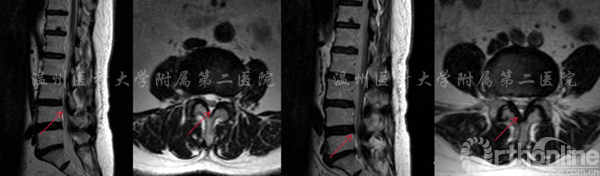

腰4/5腰椎管狭窄行单节段CBT螺钉固定

术前MRI提示:腰4/5管狭窄(左) 术后X线提示:固定良好(右)

3/4,腰4/5椎间盘突出伴椎管狭窄,行双节CBT螺钉固定。

左图:提示腰3/4椎管狭窄  右图:提示腰4/5椎管狭窄

术后X线显示CBT螺钉未松脱、断裂,螺钉位置良好